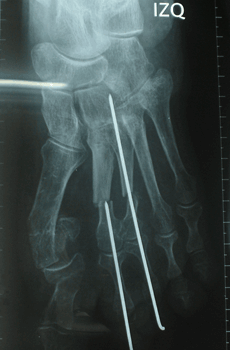

Caso 1: Hallux Valgus del Adulto